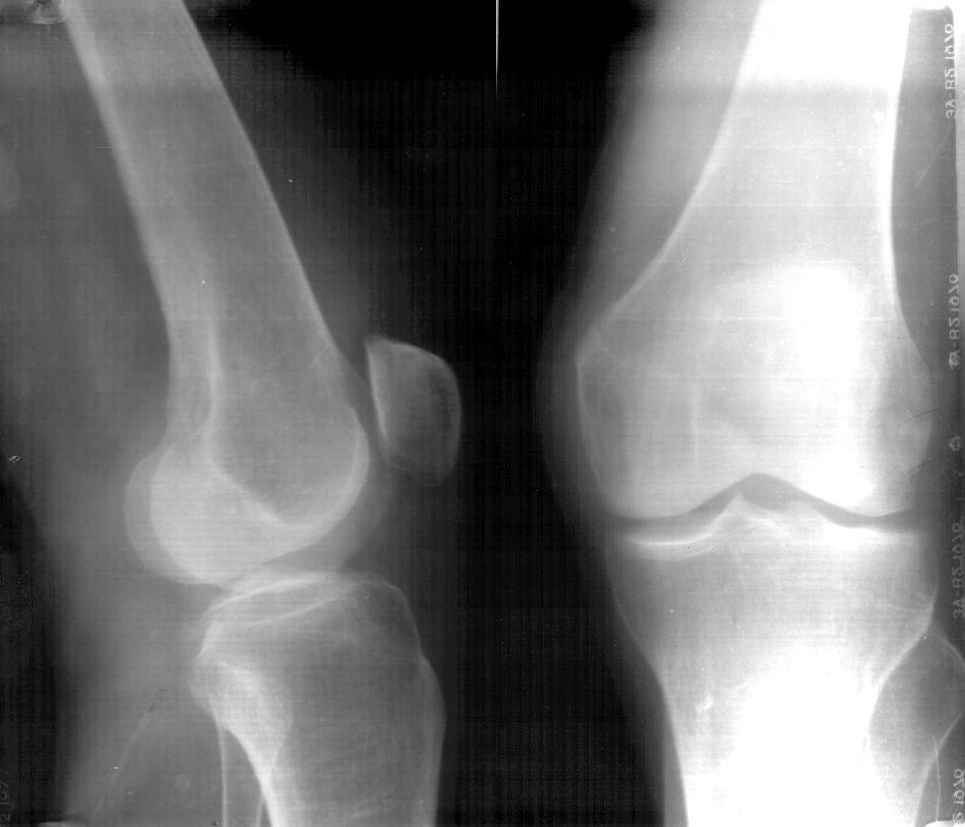

Больная К.85 лет, получила незначительную травму в конце июля 2002 года (рентгенограммы от 26.07.2002). Ушиб коленного сустава, отека не было, гемартроза не было. Лечилась местными средствами, троксевазиновая мазь, водочные компрессы. В дальнейшем развился посттравматический периартрит правого коленного сустава, синовиит правого коленного сустава. Больная на дом приглашала много различных врачей, из санаторной сети, частных хирургов, из скудных полученных данных возможно было выяснить, что получала диклофенак-натрий внутримышечно, примерно 10 раз. Несколько внутрисуставных инъекций, сколько и с каким промежутком выяснить не удалось, но более менее достоверно, что один раз вводили гидрокортизон и один раз кеналог-40. Записи практически никто не оставлял.На данный момент больная категорически отказывается от госпитализации в любое из предложенных отделений ни только для лечения, но и для обследования. Ищет врача, который назначит "правильную" мазь.Моя версия, асептический некроз наружного мыщелка правого бедра, после многократного введения гормональных противовоспалительных препаратов (рентгенограммы от 07.05.03).

AB> Моя версия, ассептический некроз наружного мыщелка правого бедра,

Многократного введения вроде и не было? Вообще, хрящевые язвы после десятков инъекций кеналога вполне ожидаемы, но тут такой остеолиз... На онкологию тоже не очень похоже... И на артрит не очень...

В возрасте 84 лет незначительная травма на фоне остеопороза могла послужить причиной перелома ( что возиожно и присутствует на предоставленных RTG

особо похоже на боковых), на этом фоне в результате блокад, пусть и не многочисленных, развился асептический некроз мыщелка бедра.

D-z:Старый несросшийся перелом наружного мыщелка правого бедра.Посттравматический ( ятрогенный?)

асептический некроз наружного мыщелка бедра.